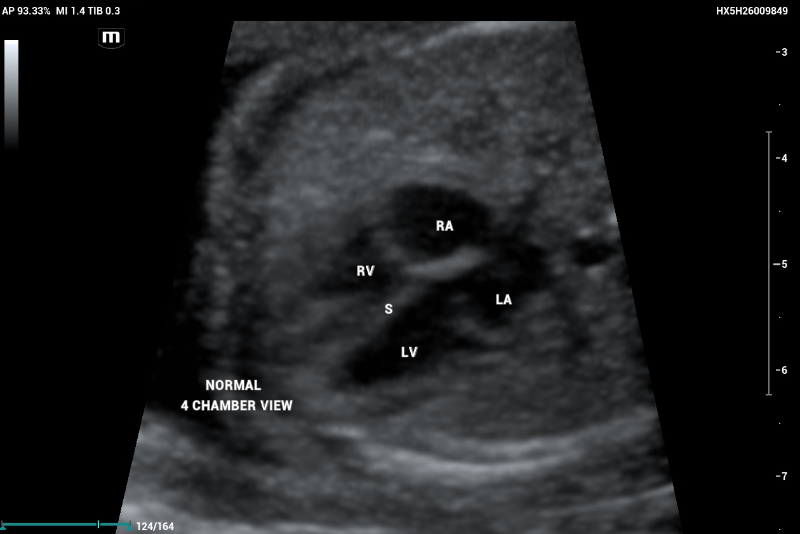

According to the ISUOG 2023 guidelines, second-trimester screening includes a standardized protocol for anatomical evaluation, incorporating fetal echocardiography. In a normal fetal echocardiogram, the ventricles should be symmetric and of equivalent size; any asymmetry is suggestive of disease (figure 1, and 2).

Example of Axial or transverse thorax image in fetal echocardiography showing a normal heart with symmetric 4-chamber view

Figure 1. Example of Axial or transverse thorax image in fetal echocardiography showing a normal hearth with symmetric 4 chambers view.